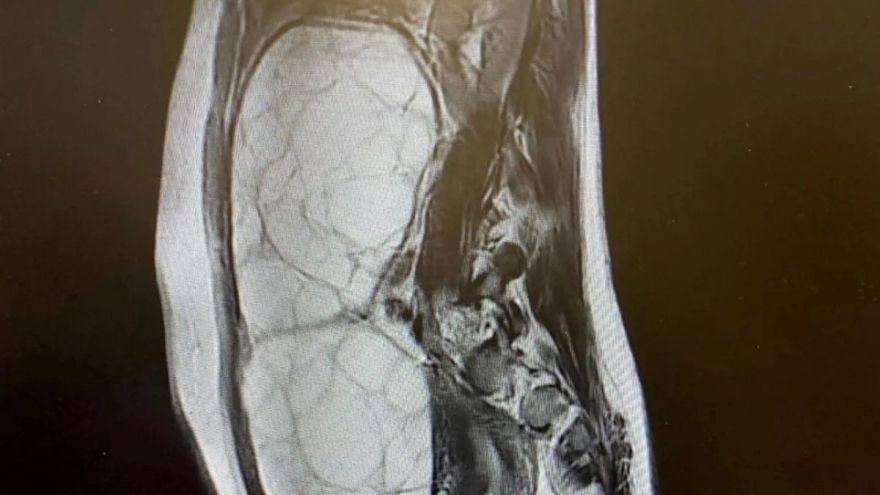

Bệnh nhân ung thư thận giai đoạn cuối hồi phục ngoạn mục nhờ kết hợp đa mô thức

VOV.VN - Nhờ kết hợp liệu pháp nhắm trúng đích và miễn dịch trước phẫu thuật, Bệnh viện Bình Dân đã giúp một bệnh nhân ung thư thận giai đoạn cuối cải thiện sức khỏe đáng kể.